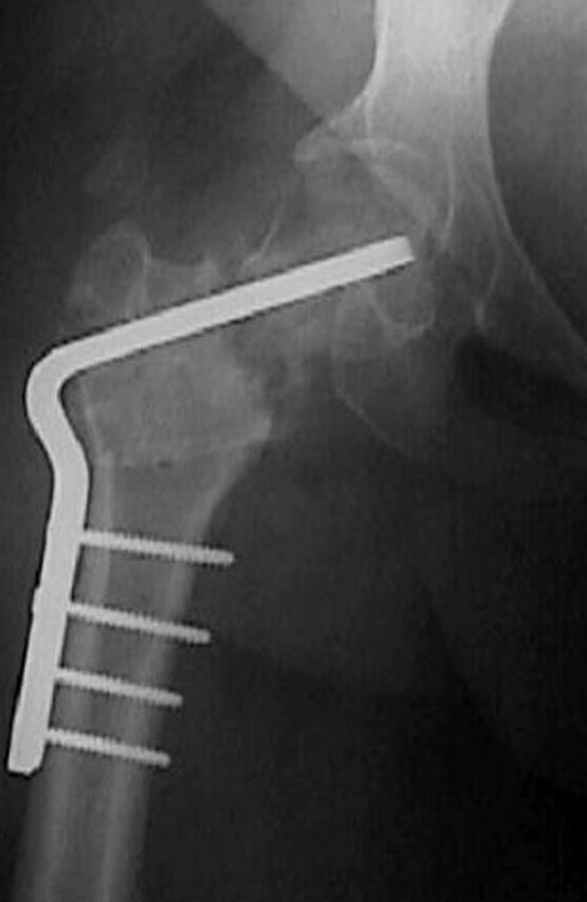

Если, например, доводится лечить больных с псевдартрозами шейки бедра, то надобность есть, и приходится. См. приложение.

На рисунке N1 предоперационный план лечения ложного сустава шейки бедра- линия ложного сустава, угол и направление введения импланта, клиновидная остеотомия в градусах и миллиметрах, второй снимок после коррекции, расчет, на сколько удлиняется конечность и размеры импланта;

N3 рисунок окончательный снимок, после операции моя рентгенограмма должен выглядеть примерно как эта картина. На N4 снимке клин перед удалением; N5 послеоперации 3 нед.; N6 окончательная рентгенограмма.